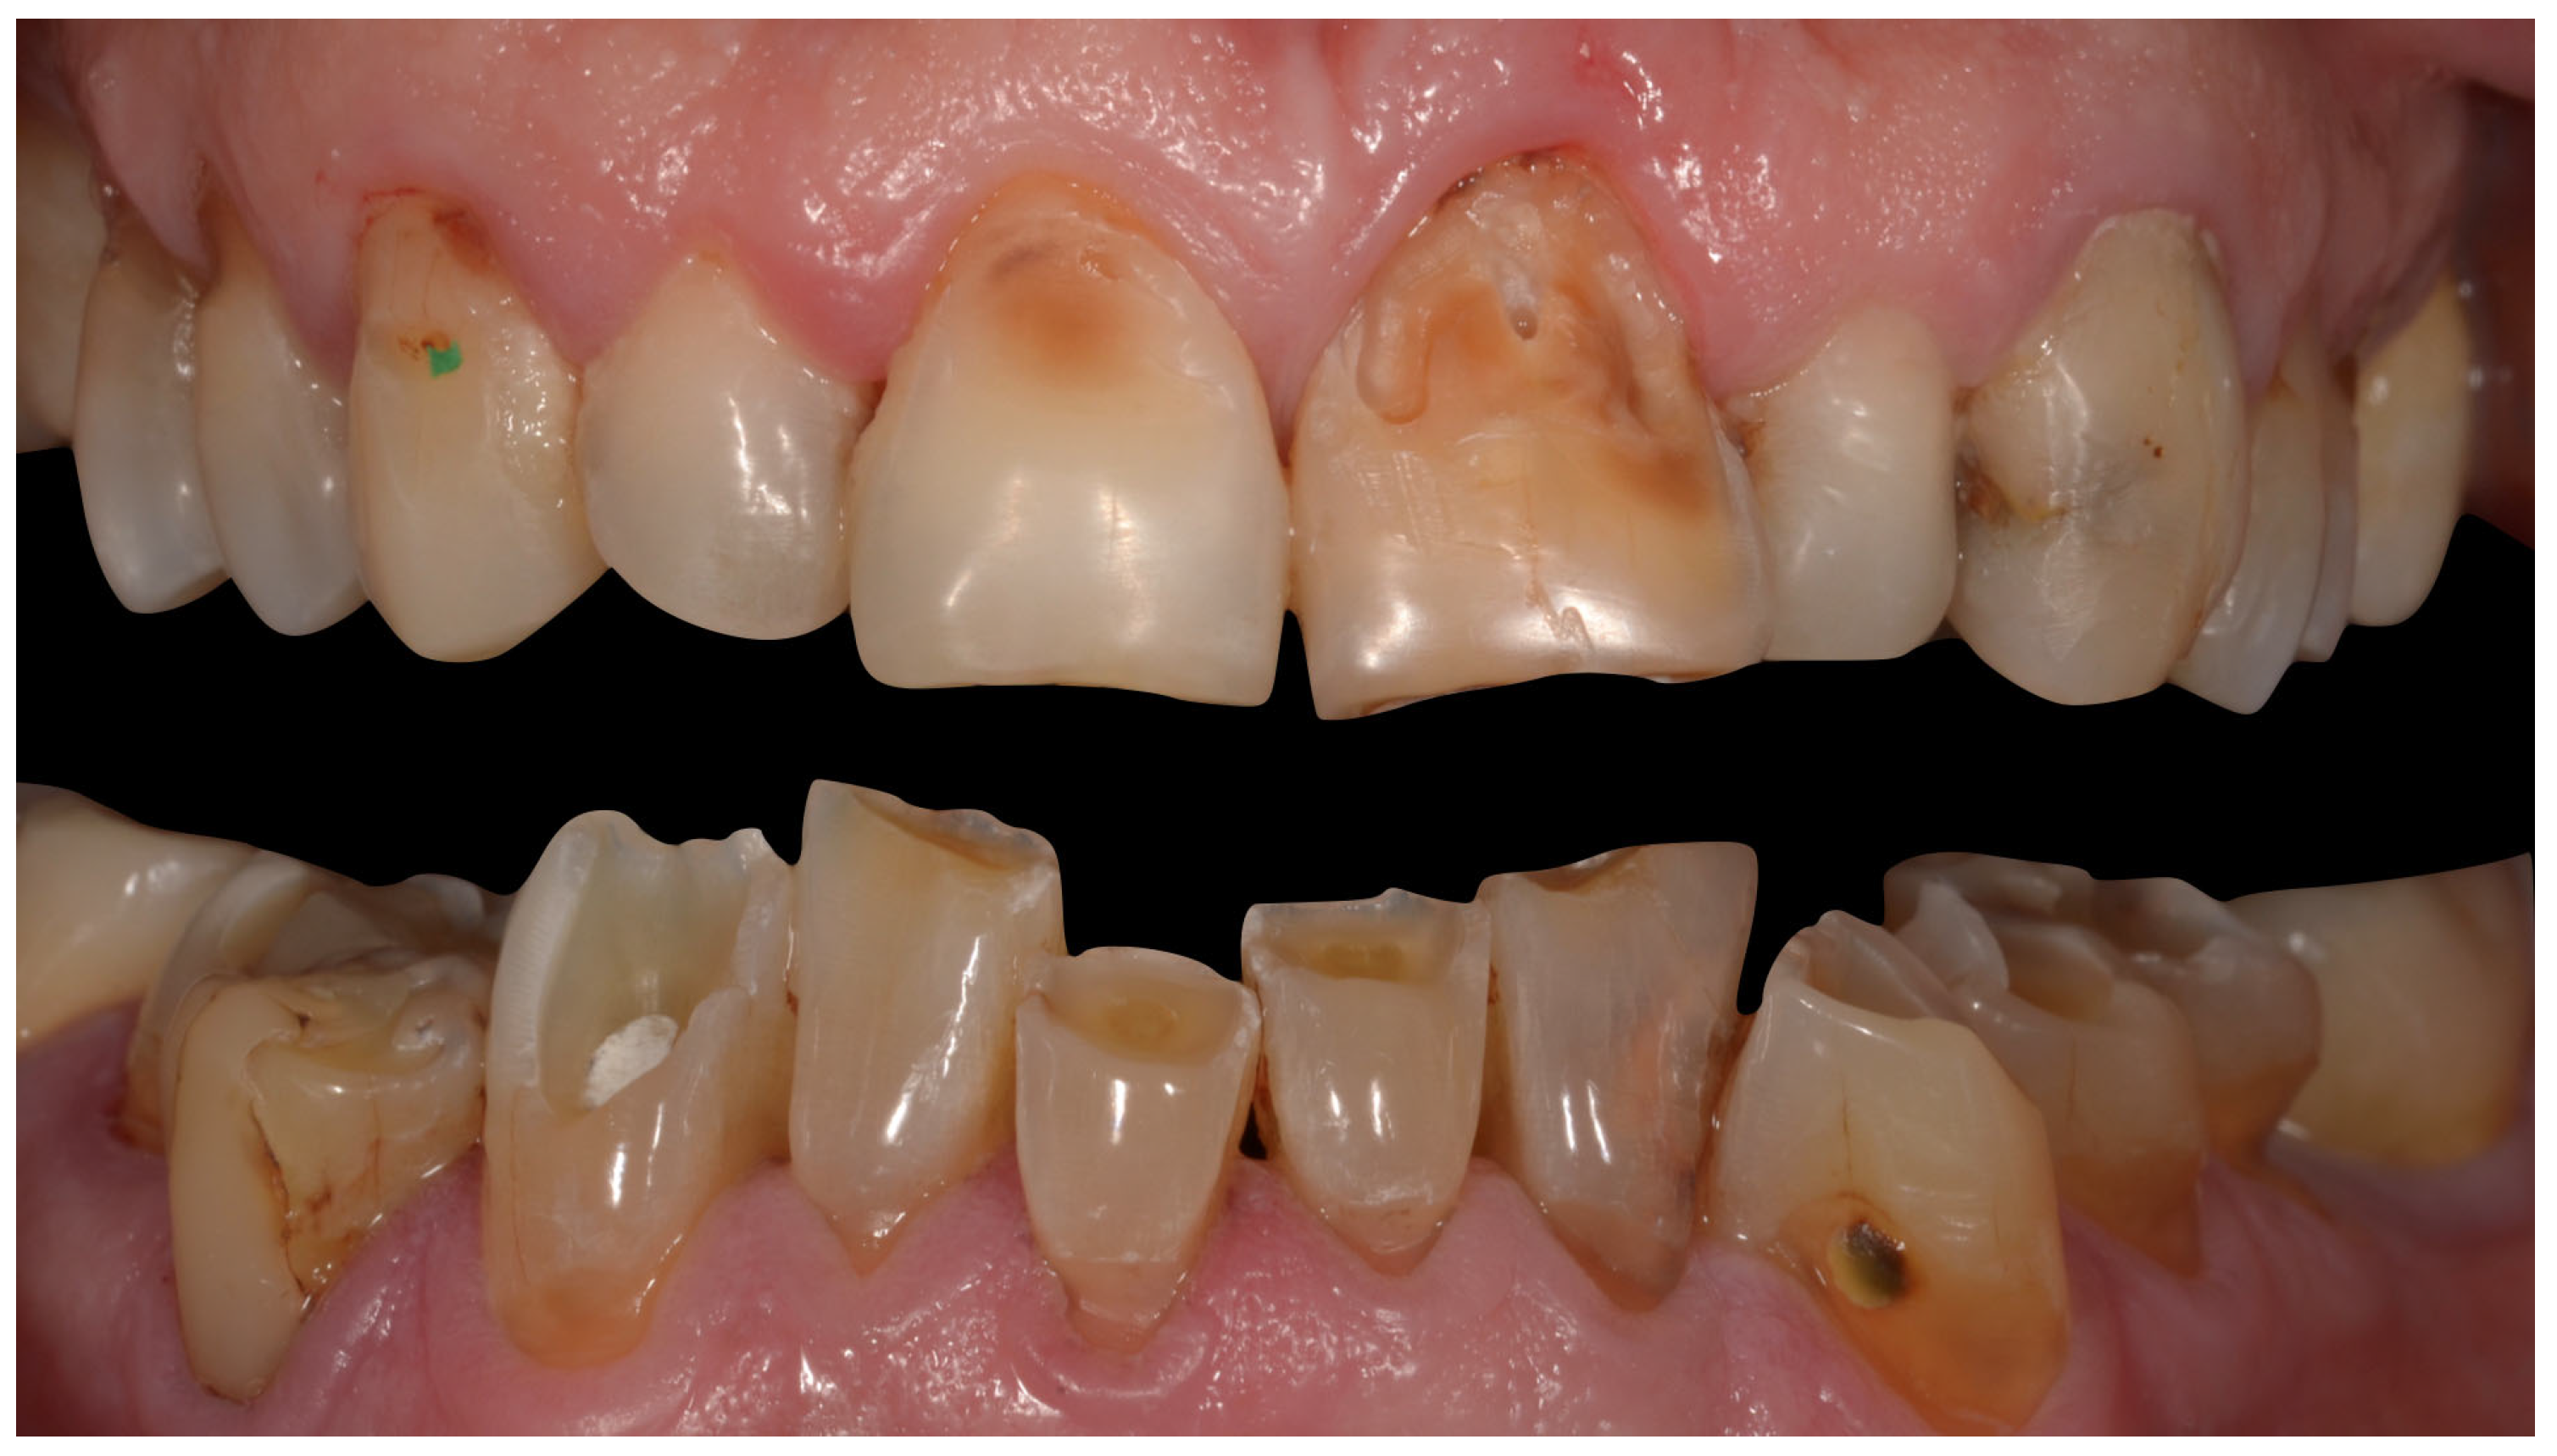

8. Teeth Enamel Wear